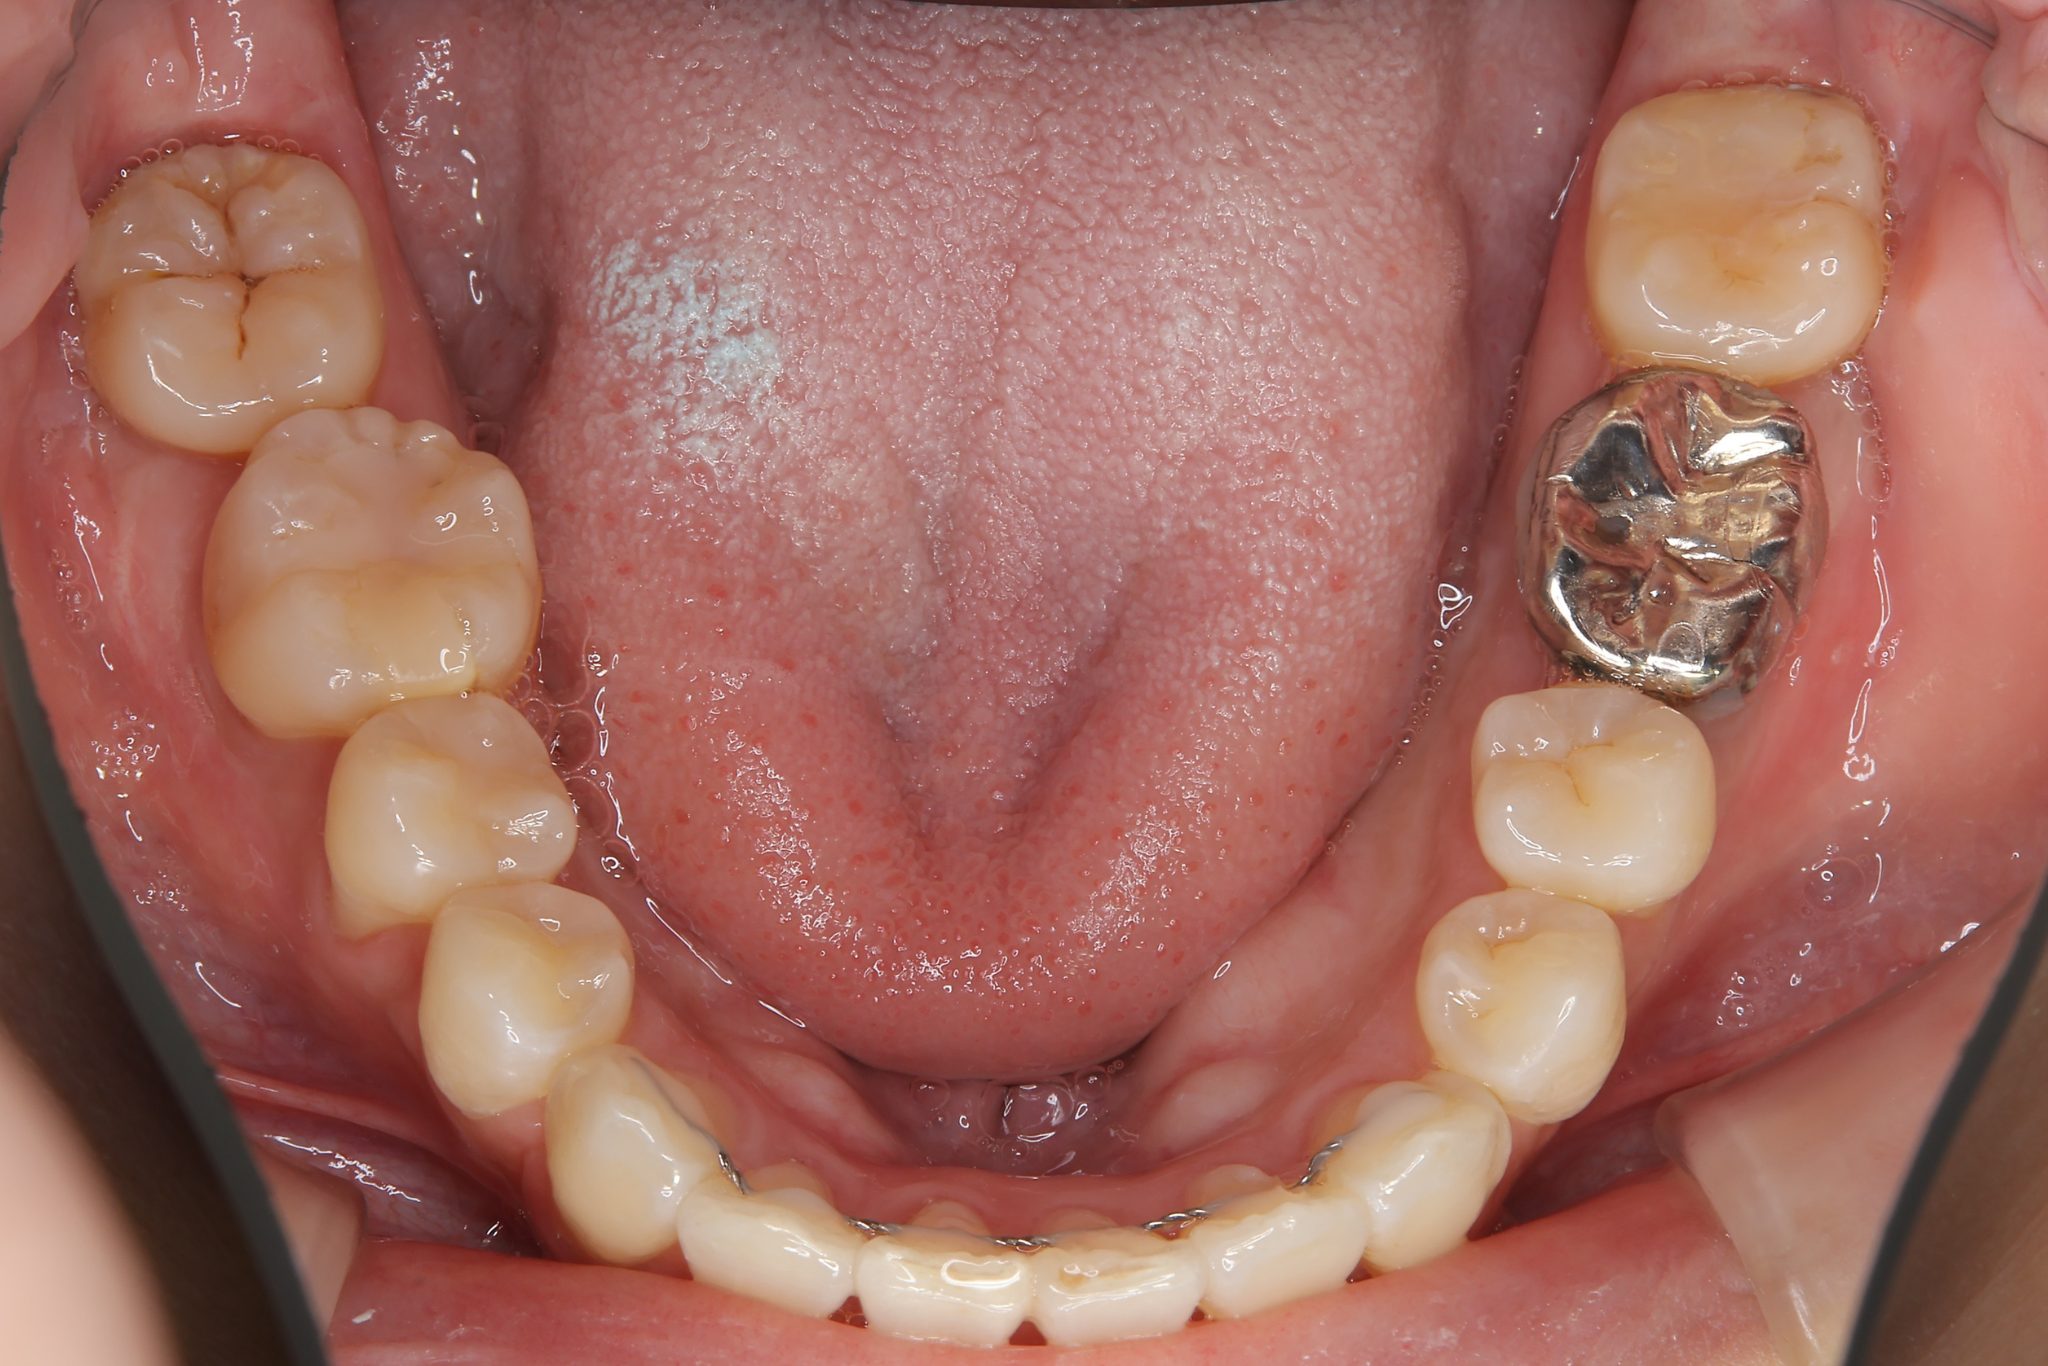

ビフォー

ワイヤー矯正治療|症例_814

主訴 八重歯

施術内容 MSEと下顎リンガルアーチを用いて上下顎骨を拡大した。

その後上顎3・4番を抜歯しマルチブラケット装置とミニインプラントを用いて

歯牙を配列した。良好な咬合を獲得した。